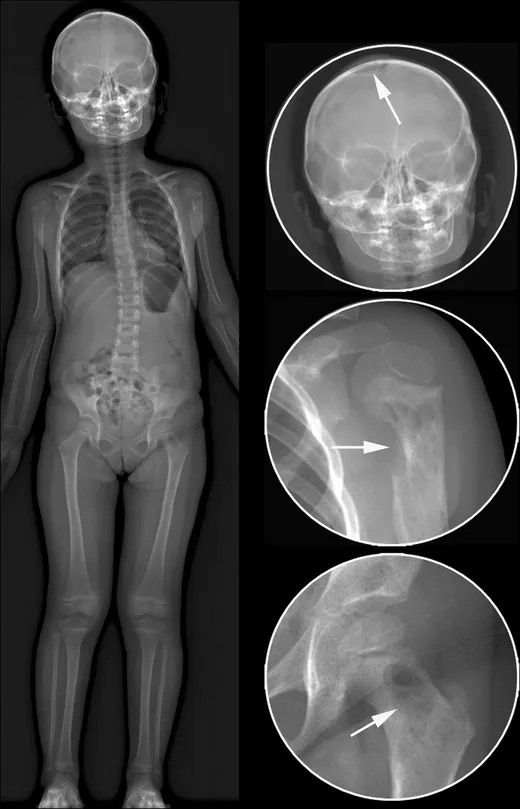

- Unifocal (Eosinophilic Granuloma): Solitary, lytic bone lesion (skull, femur); may affect skin, lung. Best prognosis.

- Multifocal Unisystem (Hand-Schüller-Christian Disease): Classic triad: lytic bone lesions (skull), diabetes insipidus, exophthalmos. (📌 HAnd: Skull lesions, DI, Exophthalmos).

- Most common LCH site: bone (skull); presents with lytic lesions.

- Hand-Schüller-Christian triad: lytic bone lesions, diabetes insipidus, exophthalmos.